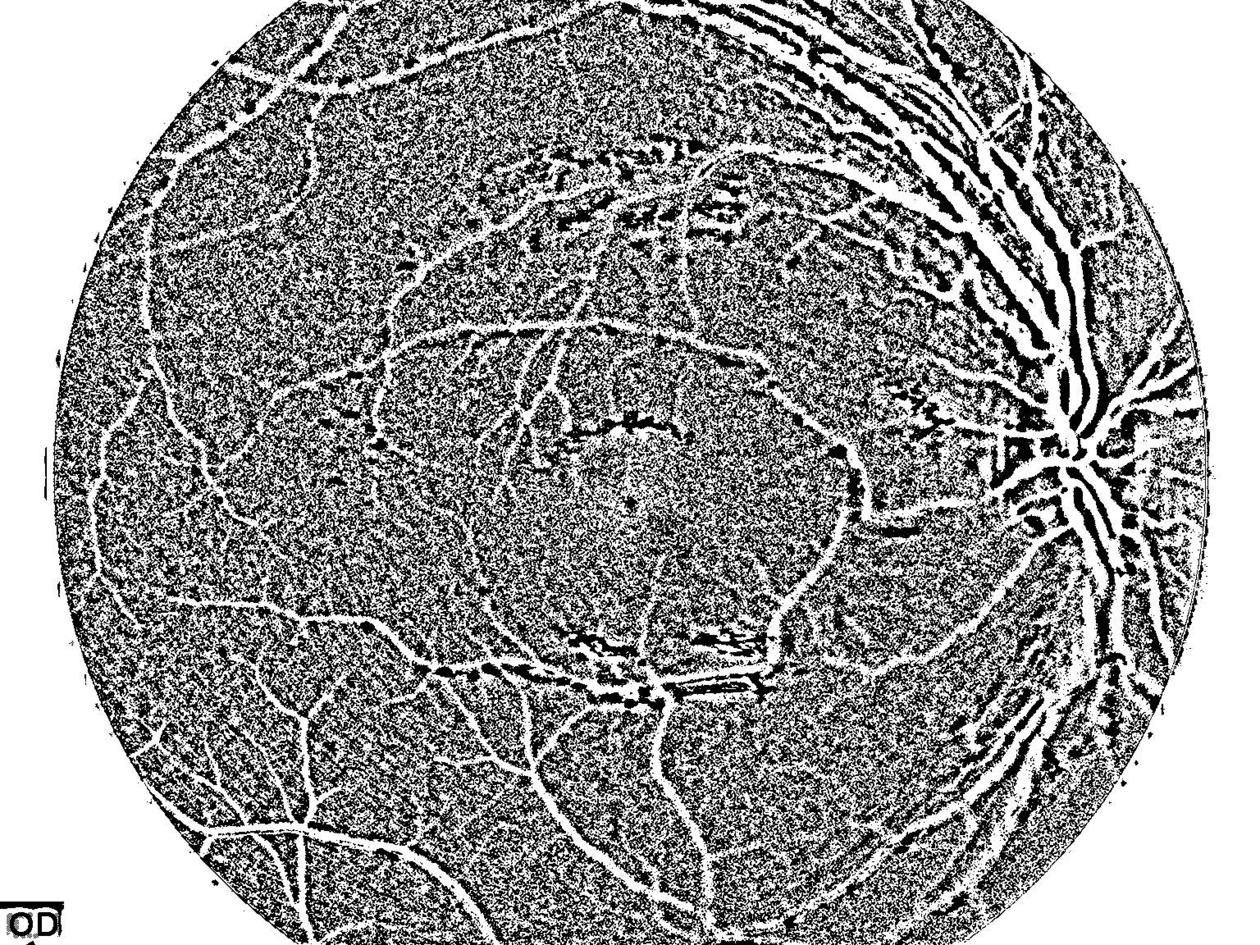

然后我用OTSU阈值提取血管,但做得不好:

self.ret, self.thresh = cv2.threshold(self.cl1, 0,255,cv2.THRESH_BINARY + cv2.THRESH_OTSU)

kernel = np.ones((1,1),np.float32)/1

self.thresh = cv2.erode(self.thresh, kernel, iterations=3)

self.thresh = cv2.dilate(self.thresh, kernel, iterations=3)结果如下:

很明显有很多噪音。我试过使用中间模糊,但它只是聚集噪音,并使它成为一个斑点,在一些地方。我该如何去除噪音来获取血管呢?